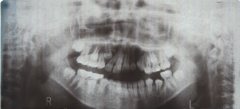

治療前 レントゲン写真

前から3番目の歯が埋伏しています